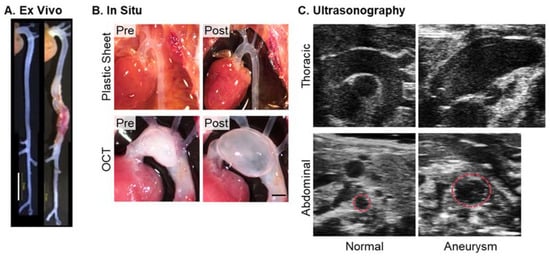

3.1. Ex Vivo Imaging

3.2. In Situ Imaging

3.3. Ultrasonography